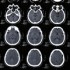

An abnormal growth within the brain and skull. It can be benign or cancerous (malignant). Even benign tumors can be life threatening depending on their location causing compression and/or elevation of the pressure in the brain (hydrocephalous). Malignant tumors can arise from cells of the brain, such as astrocytomas, or from cells transported to the brain through the blood stream or lymphatic system (metastases).

A history and physical exam will be performed. A head CT or MRI is done to diagnose the tumor. A biopsy may be required to identify the type of tumor.

CT_Scan